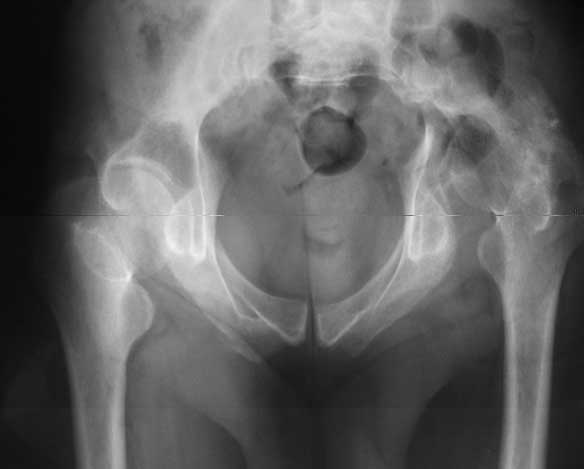

Our experience showes, that reposition and stabilization pelvis in zone of old acetabular fractures with bone grafting are very traumatic and not effective due head AVN and hip arthrosis.

In such cases we use hip arthroplasty with "Octopus" acetabular system (De Puy). This system consist of acetabular ring and cementless cup.